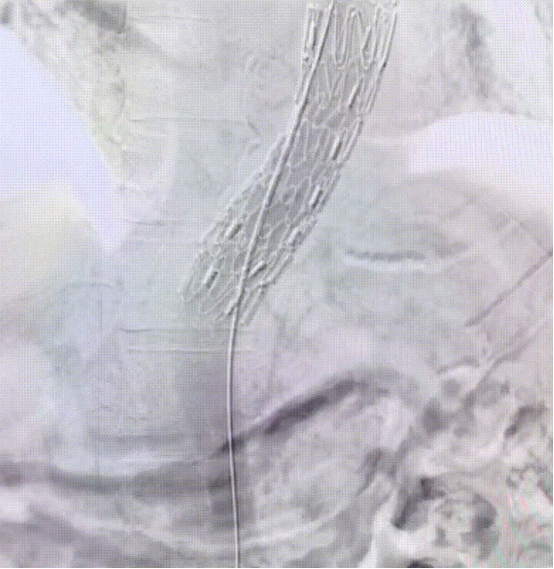

远端置入裸支架

术后CTA

术后CTA显示:支架位置形态良好,无内漏,主体支架成功封堵主动脉夹层破口,分支支架重建LSA,LSA血流通畅,裸支架扩张远端真腔,手术效果满意。